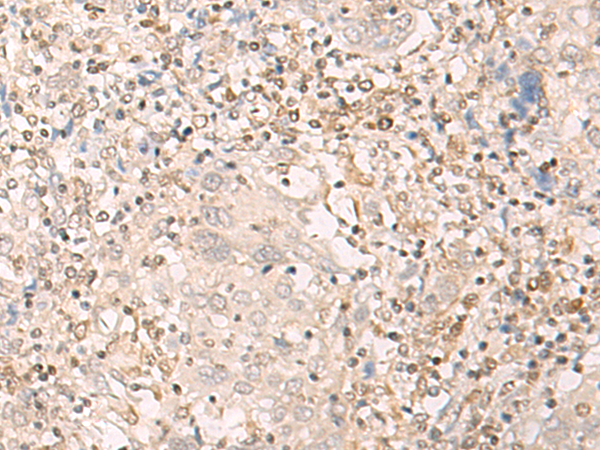

IHC positive control: |

Human cervical cancer and Human tonsil |

IHC Recommend dilution: |

30-150 |